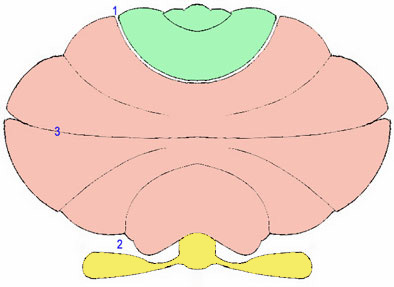

Le schma ci-contre

reproduit le planigramme de Larsell qui rsume la topographie des trois

principaux lobes & fissures. - Lobe antrieur (en vert) - lobe postrieur (en rose) -

complexe floculo-nodulaire (en jaune) |

Sch.13 – Planigramme de Larsell |